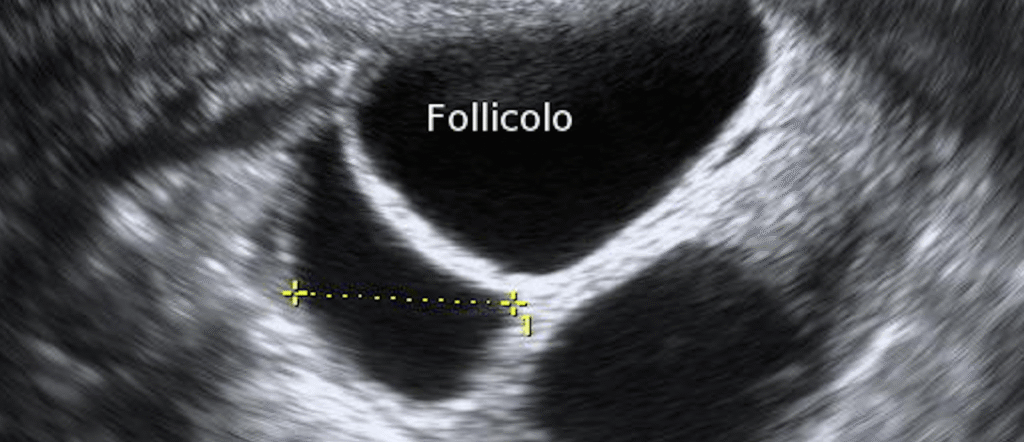

Monitoraggio ecografico e/o ormonale della crescita follicolare per definire i giusti dosaggi farmacologici (in caso sia prevista la stimolazione ormonale) e il momento preciso della IUI